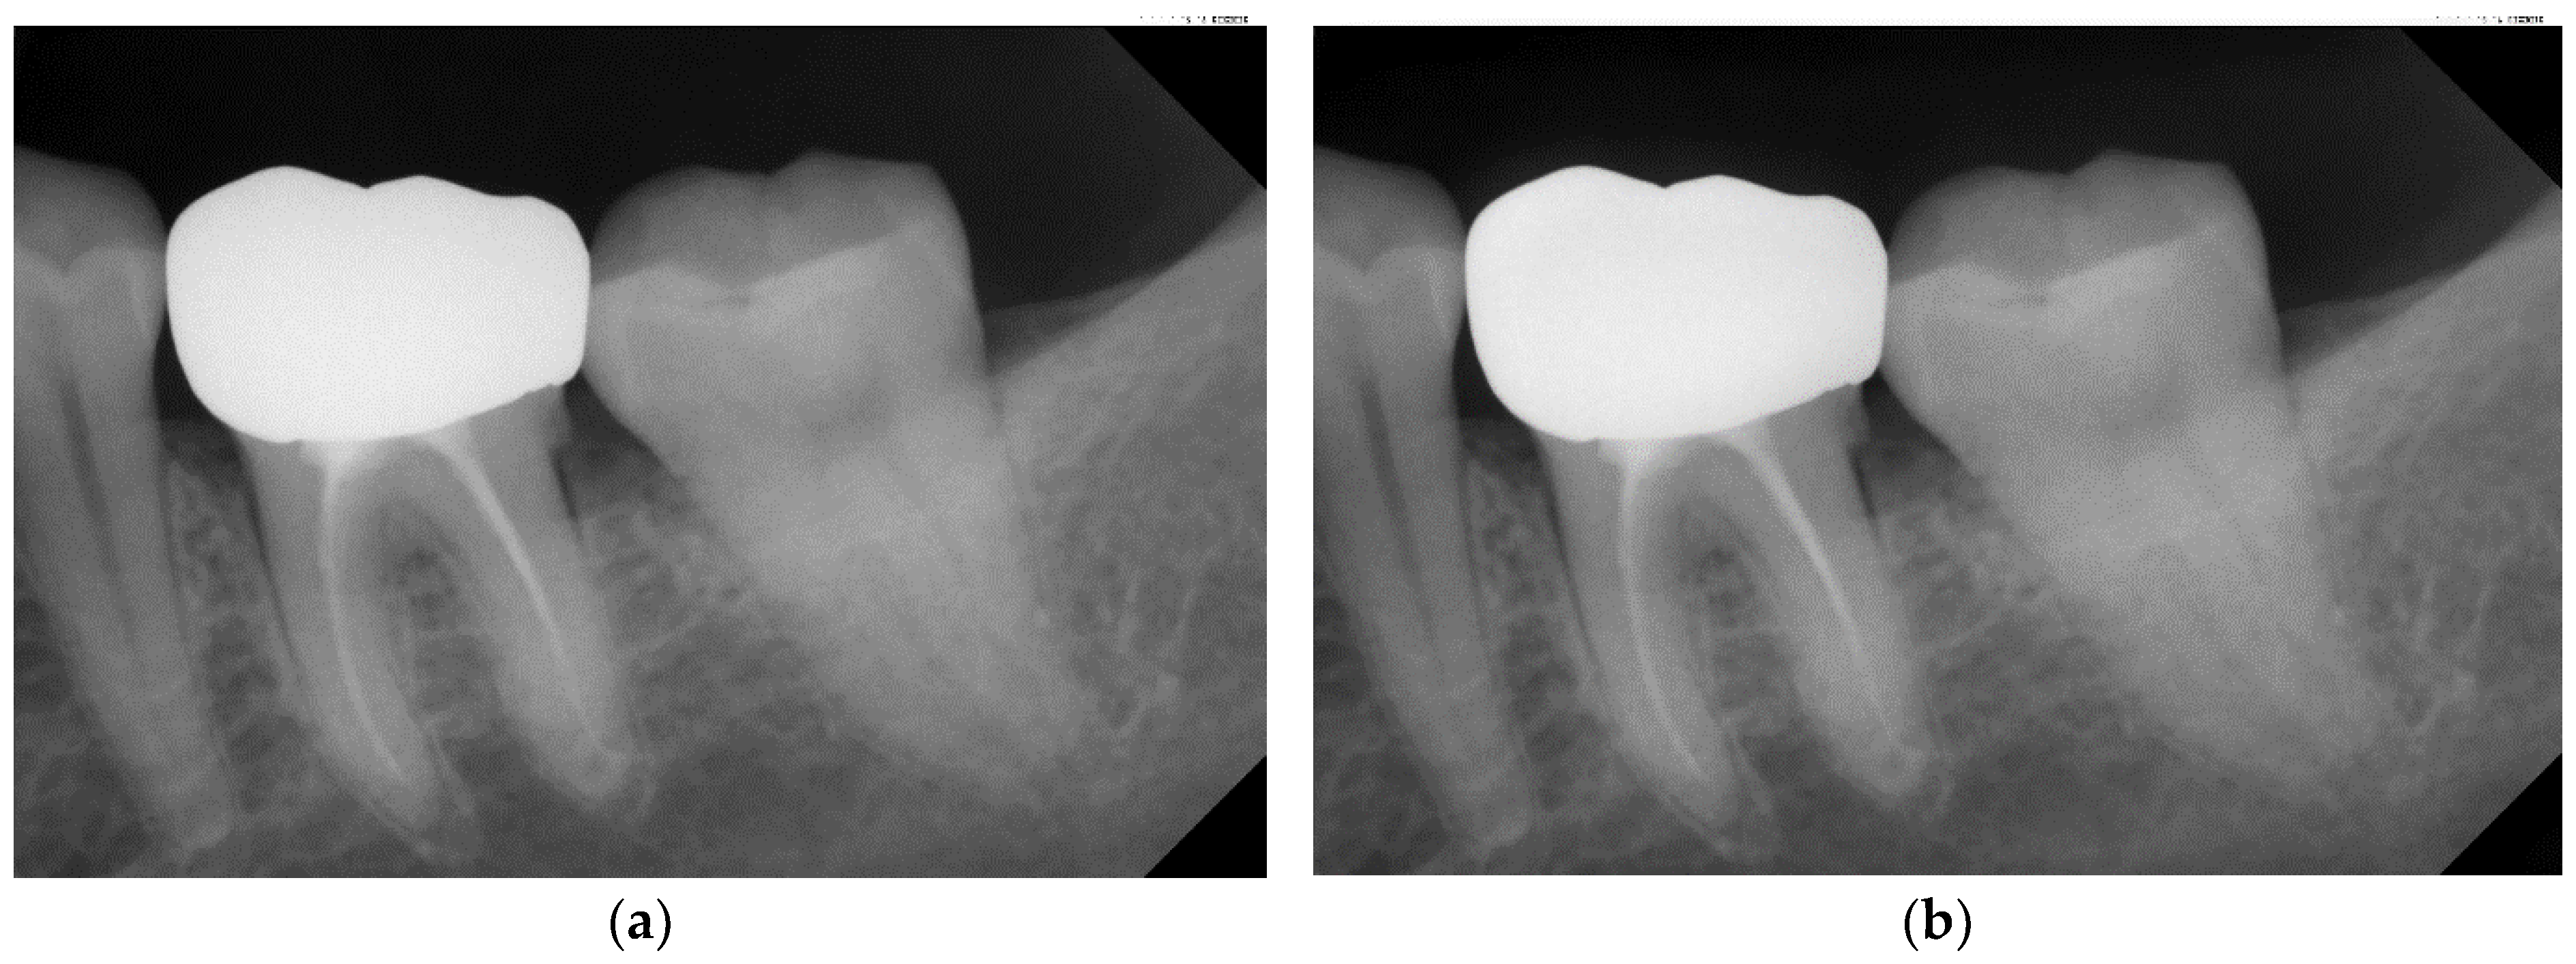

| Original Images | Gaussian High-Pass Filter | Gaussian High-Pass Filter + Mask | |

|---|---|---|---|

| Validation Accuracy | 84.16% | 87.21% | 94.97% |

| Validation Loss | 0.7634 | 0.4578 | 0.1822 |

| Model | GoogLeNet | GoogLeNet | GoogLeNet |

| Image | ![]() | ![]() | ![]() |